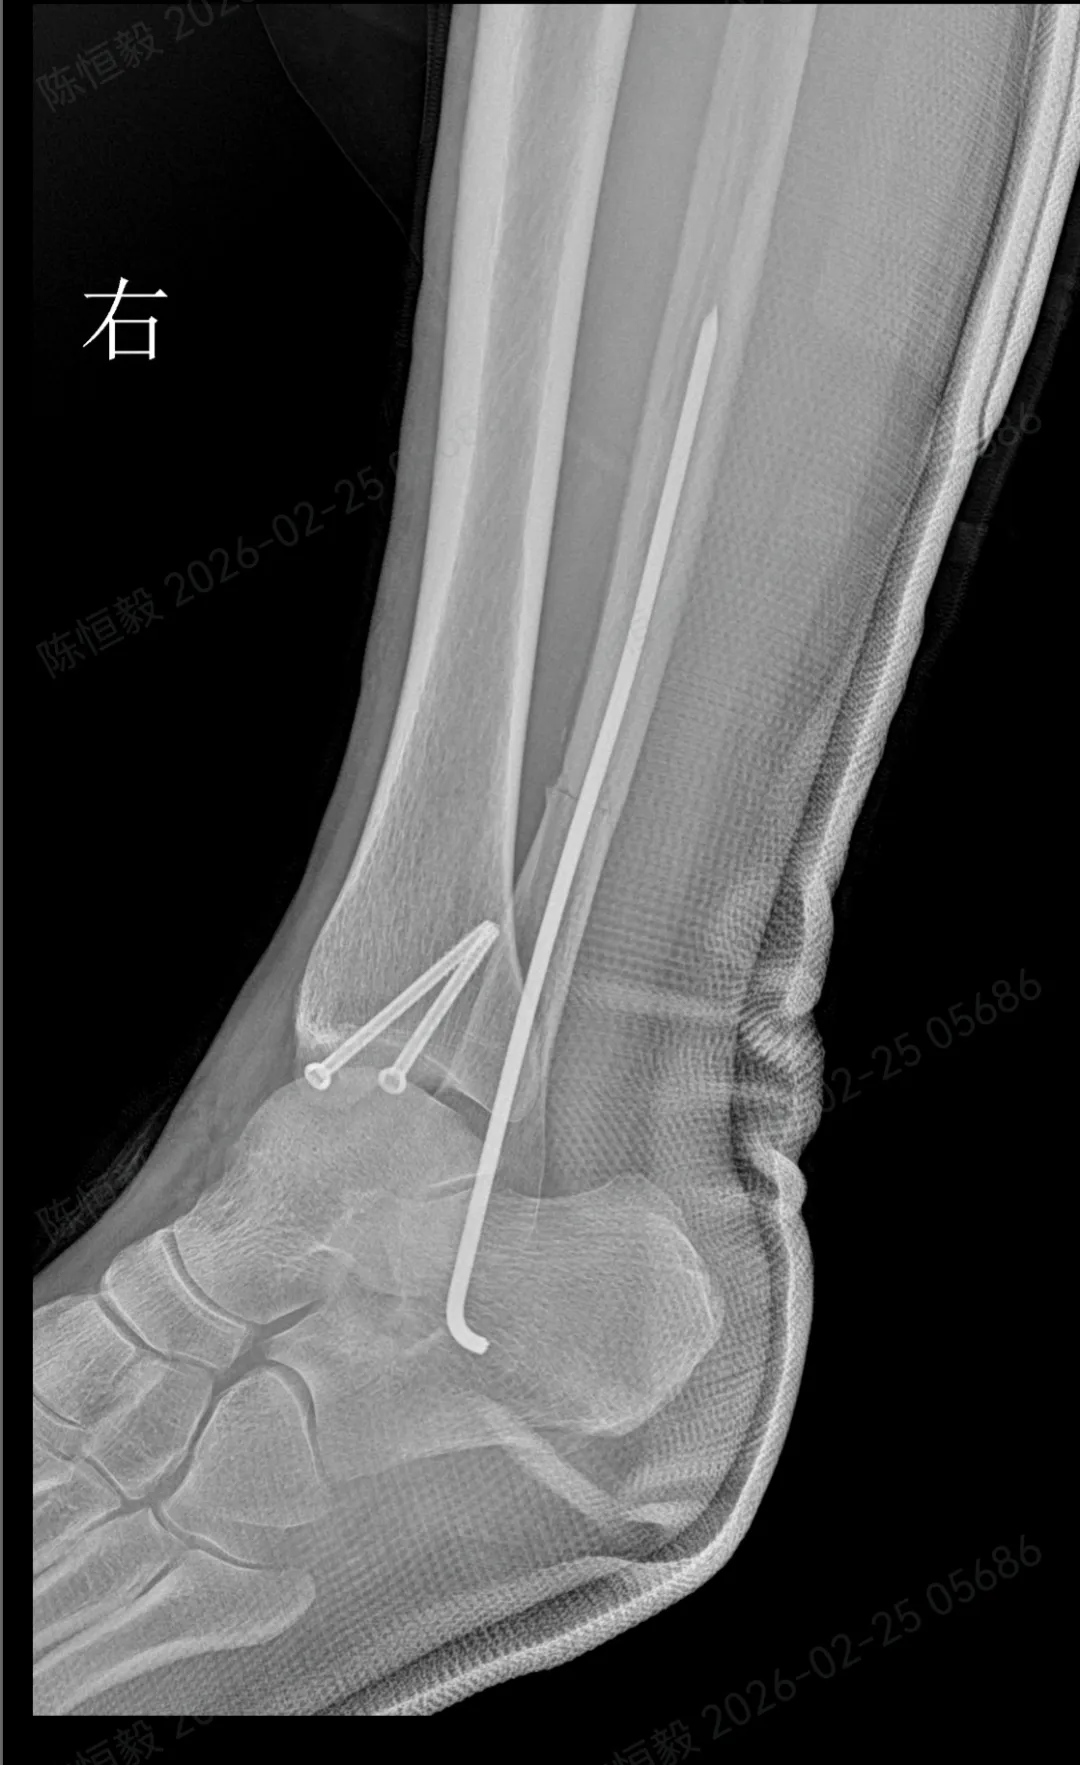

针对王女士的踝关节骨折情况,由副主任医师陈涛主刀,足踝外科团队为其实施了关节镜辅助下机器人导航微创闭合复位内固定术

• 依托机器人导航系统,规划螺钉置入通道,避开关节面与重要组织;

• 最后通过另外两个 5 毫米的小孔置入空心螺钉,完成骨折端的稳定固定。

整个手术仅通过三个 5 毫米的小切口完成,最大程度降低了手术创伤。

术后的恢复情况也契合了王女士的期待:

• 术后第二天,王女士便可在床上进行踝泵训练;

• 术后第三天,在充气靴保护下能够部分负重行走;

• 术后两周复查,手术切口愈合状况良好,几乎无明显痕迹。